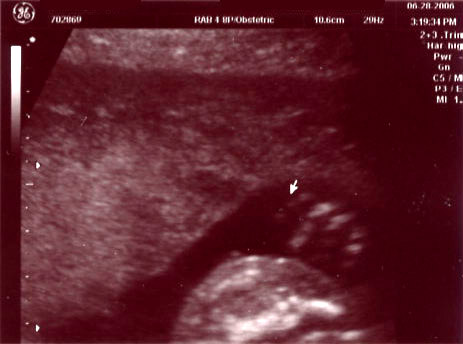

| June 28, 2006 - Twenty Week Ultrasound: IT'S A BOY!!! |

took us right away. Within 44 seconds of the technician turning on the

ultrasound machine, she showed us the picture of the legs spread wide open

and it was obvious that we were having a boy!! He was so active

The boy parts :) |